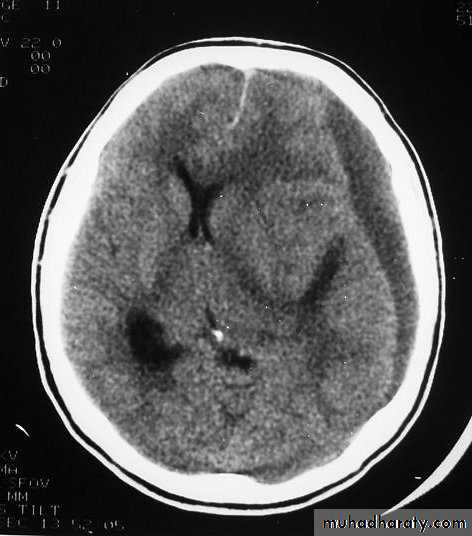

1. Diffuse Axonal Injury

Prolonged post-traumatic state in which there is loss of consciousness from the time of injury that continues beyond 6 hours.

Occurs as a result of mechanical shearing at the grey-white matter interface.

This causes disruption and tearing of axons, myelin sheaths and blood capillaries.

Severity can range from mild damage with confusion to coma and even death.